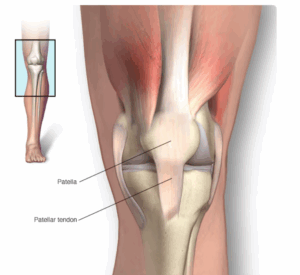

Patellar tendinitis

Patellar tendinitis is an injury to the tendon that joins the kneecap, also called the patella, to the shinbone. The patellar tendon works with the muscles at the front of the thigh to straighten the knee.

Patellofemoral Pain Syndrome

Patellofemoral (puh-tel-o-FEM-uh-rul) pain syndrome is pain at the front of the knee, around the kneecap. The kneecap also is known as the patella. Patellofemoral pain syndrome is sometimes called runner's knee.